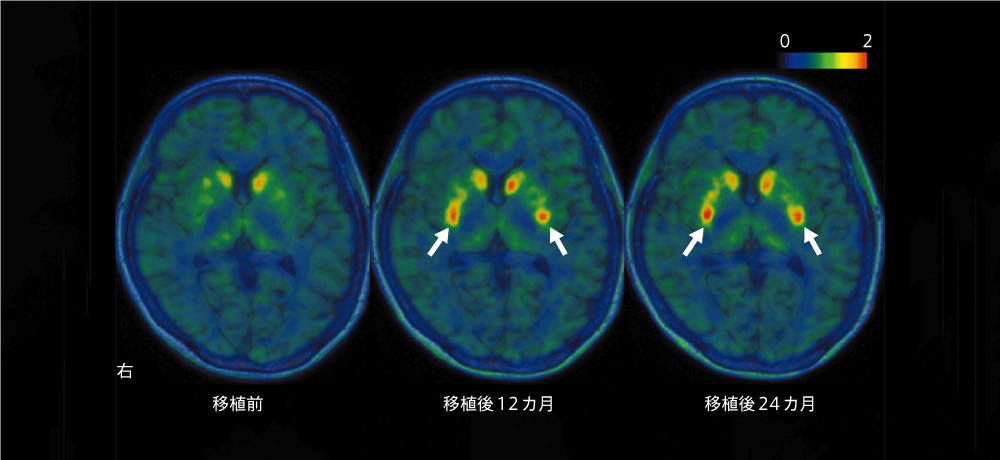

図2 PET画像で捉えた被験者の脳内のドーパミン産生

左から、細胞移植前、移植後12カ月、移植後24カ月の画像。パーキンソン病になるとドーパミンの産生が低下し、PET画像では黄色から緑色に表示されるが、細胞移植後にはその部位が赤くなっている(矢印)。つまり、移植細胞が脳内でドーパミンを産生していることを確認できた。 Credit: Ref. 8

副次評価項目の結果も納得できるものでした。磁気共鳴画像法(MRI)で、細胞増殖マーカーを用いた異常な細胞増殖と、ミクログリア活性化マーカーを用いた炎症の有無を調べましたが、いずれも確認できませんでした。また、移植前、および移植1年後と2年後に、陽電子放出断層撮影(PET)を用いて被殻におけるドーパミンの産生量を調べたところ、解析した6人全員で産生量が増えており、24カ月後の平均増加率は44.7%でした。特に、細胞を高容量で移植した患者で顕著な増加が見られました。